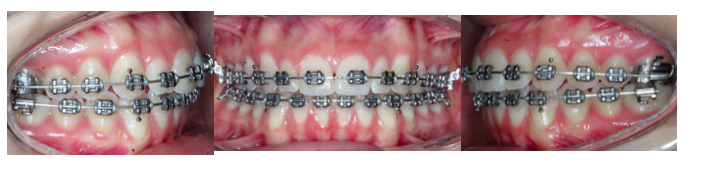

Brackets

Metálicos Transparentes Linguales Autoligado Alineadores invisibles

¿COMO SE SI NECESITO TRATAMIENTO DE BRACKETS/INVISALIGN?

si tengo DIENTES CHUECOS

Si tengo DIENTES AMONTONADOS

Si tengo un TRATAMIENTO MAL HECHO